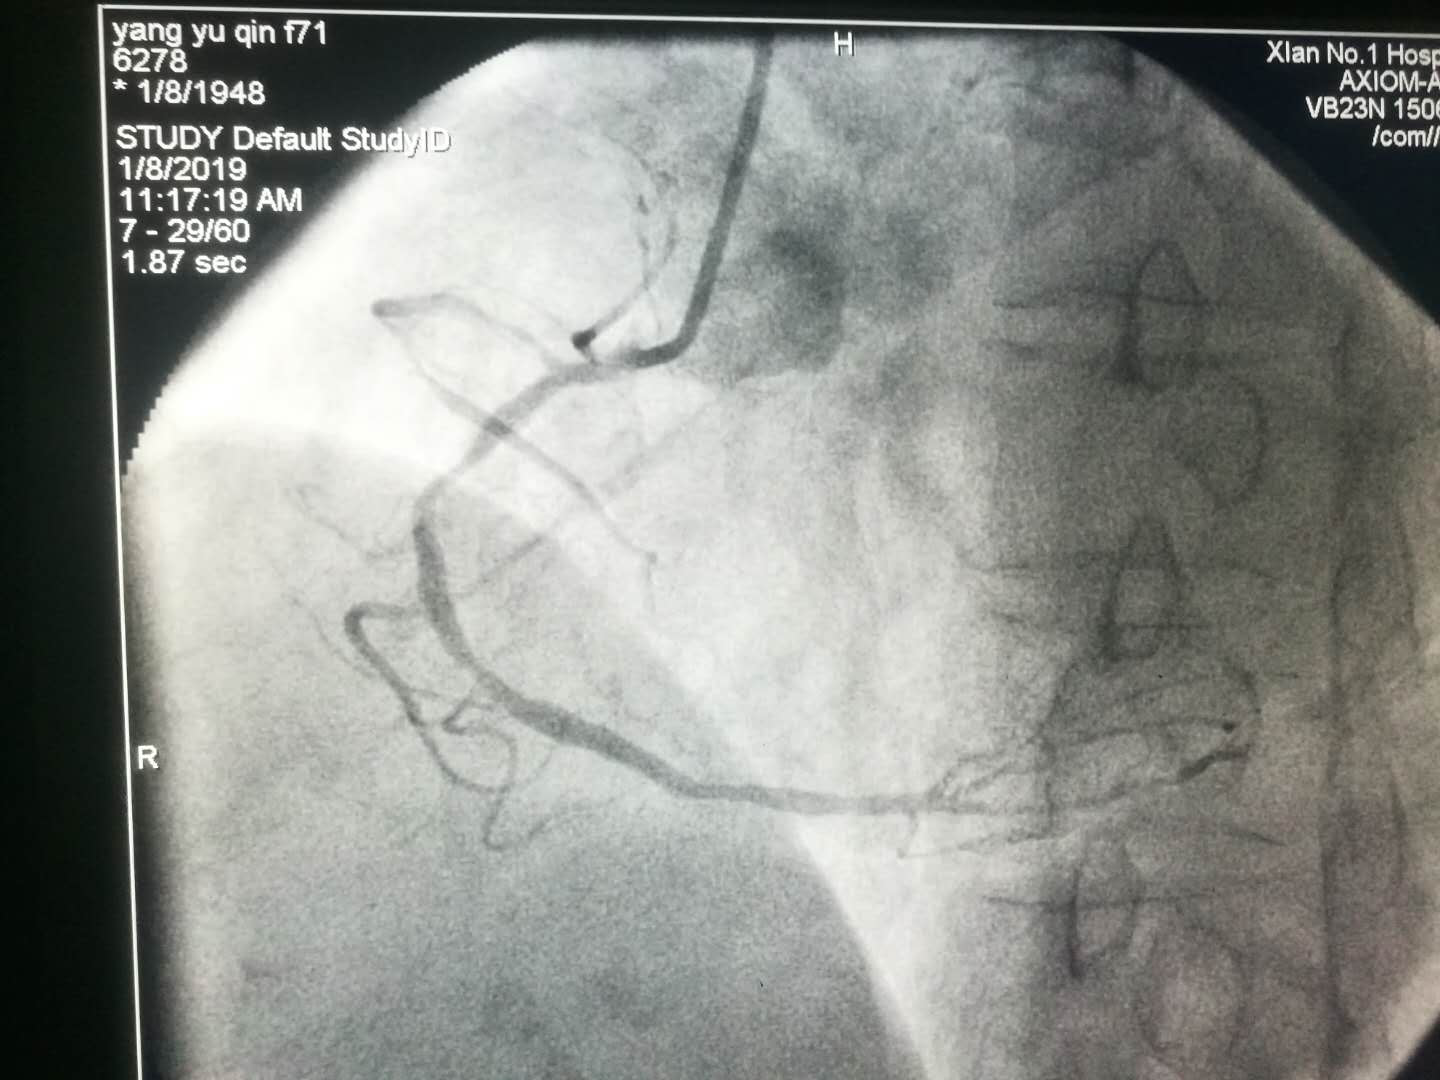

2019新年伊始,文理病区开展了首例冠状动脉造影术及冠状动脉支架植入术。

1月4日中午,文理门诊贾丽萍主任接诊一名胸痛患者, 经马会军主任急会诊,患者为急性冠脉综合征,立即组织救治并开通绿色通道。总院火速派出救护车接患者实施急诊冠状动脉造影术。患者及家属感动地说:“没有想到在分院就诊能享受到三甲医院的诊疗技术与护理服务。”对我院医疗护理服务的诊治技术、诊疗过程的服务及如此便捷快速的诊治流程,感到非常满意。虽然分院距离总院有数千米路程,但丝毫没有影响到分院三级医院服务的延伸。

1月8日上午患者术后在李同华主任的协助下完成文理病区首例冠状动脉造影术加冠状动脉支架植入术。术后患者转入心内四病区监护48小时,1月9日患者平安转回我科继续治疗。整个转诊过程无缝衔接,配合顺畅心血管病医院的各位主任护士长们纷纷表示,只要文理病区需要,术后患者可以转往心血管医院任何一个病区监护。距离无法阻隔我们发展的脚步,无法阻隔我们团结一致为患者服务的信心。